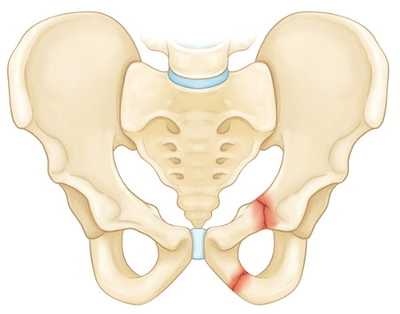

На рисунке — Перелом верхней и нижней ветвей лонной кости

Стабильные переломы. Данный тип переломов обычно отличается наличием лишь одной линии перелома и сохранением анатомии тазового кольца. Низкоэнергетические переломы — это обычно стабильные повреждения. К стабильным переломам относятся следующие: